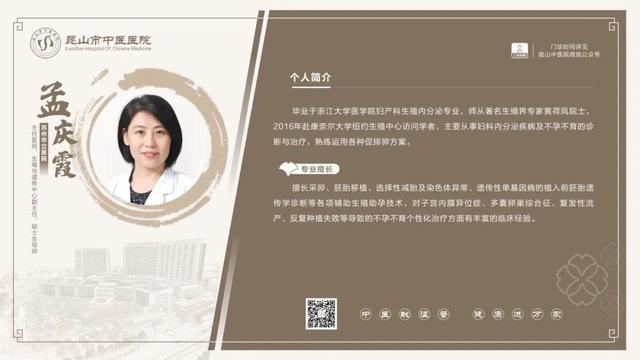

6��23��-6��29��������ר�ҳ���һ����

������鿴��ͼ���Ե���ʵ�ʳ���Ϊ��

6��23��-6��29�������dz���ר�ҽ���